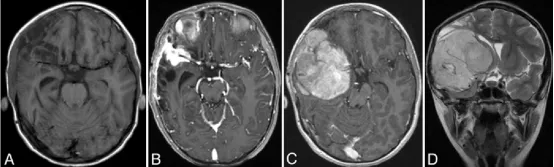

图2.A:弹簧圈栓塞术后1.5个月获取的轴位T1加权平扫MRI图像,显示右侧额叶残余出血的演变,周围伴有额叶和颞叶脑软化。

B:栓塞术后11个月获取的轴位T1加权钆增强MRI图像,显示右侧外侧裂内有一个2.3×2.7×1.8厘米(前后径×横径×头尾径)的呈显著强化的软组织肿块,包绕右侧大脑中动脉三分叉并累及邻近硬脑膜。

C和D:术后13个月获取的轴位T1加权钆增强(C)和冠状位T2加权(D)MRI图像,显示一个8×7.2×7厘米(前后径×横径×头尾径)的呈显著强化的肿块,包绕右侧大脑中动脉,并延伸至前颅窝和中颅窝。可见明显的占位效应、中线移位及凸面硬脑膜受累。